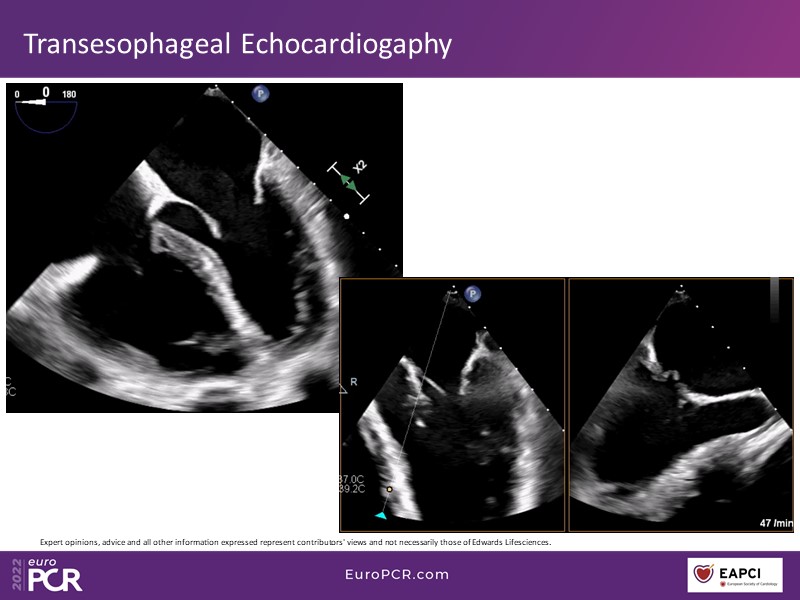

With study outcomes and clinical cases, this EuroPCR 2022 session will enable you to discuss the anatomical considerations that define suitable candidates for treatment of mitral regurgitation with the PASCAL platform and highlight key differentiators and tips and tricks for its use.

- To discuss which anatomical considerations define suitable candidates for the treatment of mitral regurgitation with the PASCAL platform

- To attend case-based discussions that will highlight key differentiators and tips and tricks when using the PASCAL platform to treat mitral regurgitation